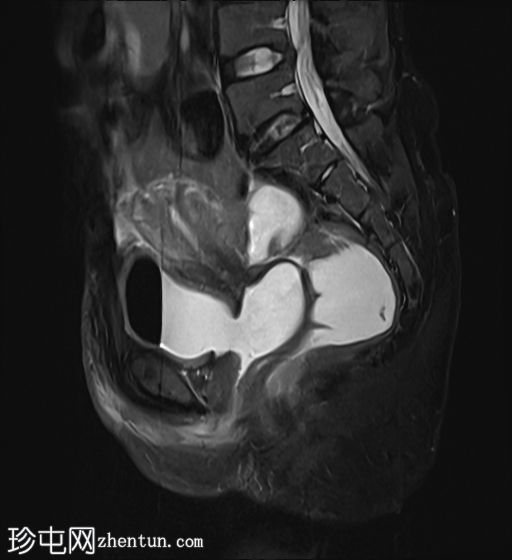

矢状位

T2加权像

2.jpg

膀胱后壁与阴道前壁之间存在宽阔的瘘管。膀胱内可见气液平面。

阴道后穹窿上部与直肠中段前壁之间可见另一条较小的瘘管。在重扫描T2加权像上也可见。

子宫未见局灶性病变。

左侧卵巢可见液性囊肿。

盆腔少量游离液体。